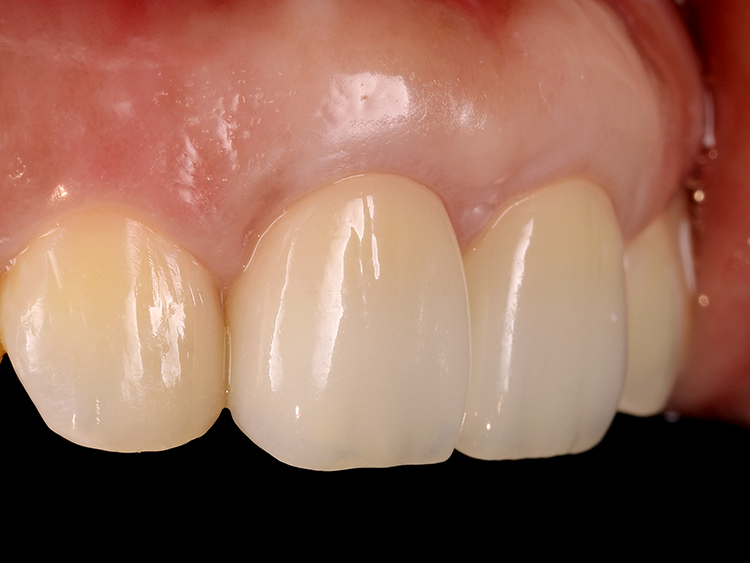

治療完了後の状態

治療後の状態です。

厚みとハリのある健全な歯周組織が回復しました。今回は両歯ともに歯根の長さが短いことから、互いに負担を分散し安定性を高めるため、連結冠としました。これにより咀嚼機能が向上し、患者さんは安心して食事ができるようになりました。

レントゲン検査の結果、根の先端にあった病変は治癒し、歯根の周囲に新たな骨の添加が認められます。これは、根管治療で用いた抗菌作用のあるMTAセメントが、カルシウムイオンを持続的に放出することで周囲の硬組織再生を誘導したためと考えられます。